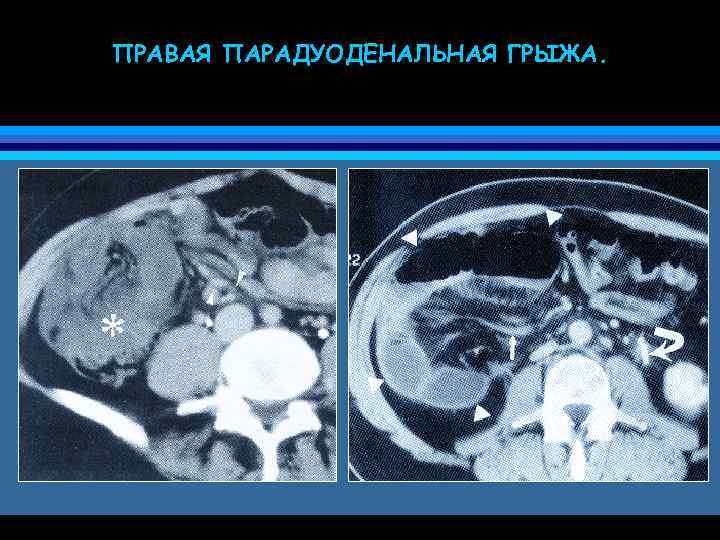

ПРАВАЯ ПАРАДУОДЕНАЛЬНАЯ ГРЫЖА.

ПАРАДУОДЕНАЛЬНЫЕ ГРЫЖИ • 50% всех внутренних грыж • врожденные грыжи, обусловленные проникновением петель тонкой кишки под восходящую или нисходящую толстые кишки при неполной ротации 12 -перстной кишки во время эмбрионального развития • левая парадуоденальная грыжа область парадуоденальной ямки (fossa of Landzert) • правая парадуоденальная грыжа область мезентерикопариетальной ямки (fossa of Waldeyer)